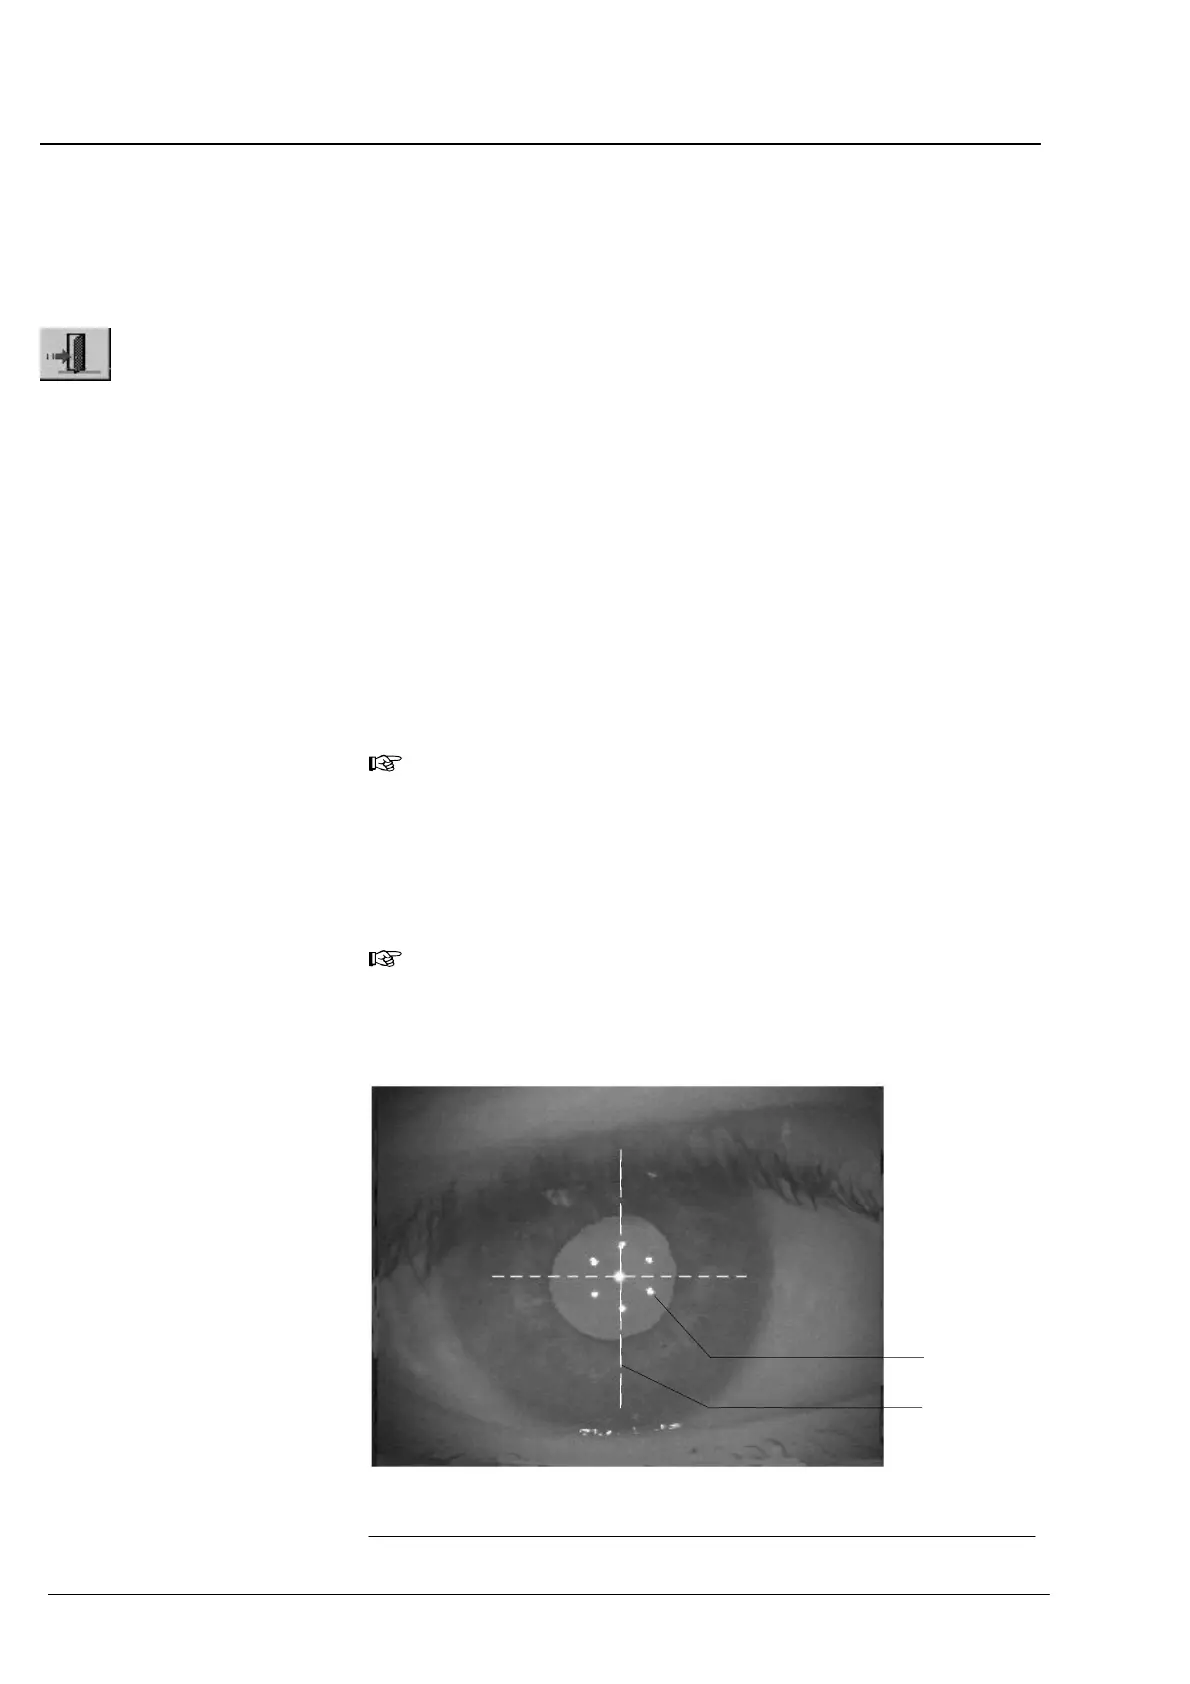

La distance entre l'appareil et le patient est variée jusqu'à ce que les

6 points (1,ĂFig. 14). Ainsi, on peut contrôler si le patient fixe

correctement.

Les 6 points lumineux devraient être à peu près centrés sur la

pupille et la réticule (2, Fig. 14). Ainsi, on peut contrôler si le

patient fixe correctement.

Fig. 14 Image vidéo de l'Ĺil dans le cas d'un appareil correctement réglé

1 Cercle en point pour focusser

2 Réticule